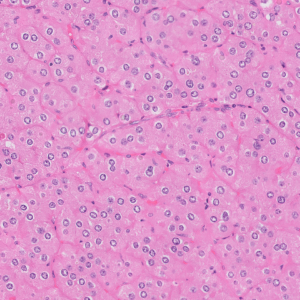

53-year-old female with renal mass